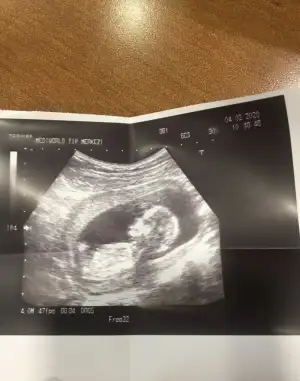

Bide bunlara bak bakalım cnm12hafta 6günlükEki Görüntüle 2585761

Kaç haftalık sanki kız gibi 12 hafta paylaşınBanada bi tahminiz var mı![]()

13 haftalık :) doktor söylemedi cinsiyetini yanıltıcı olabilir dedi. Tahmini ni bile söylemediKaç haftalık sanki kız gibi 12 hafta paylaşın

Başka usg varmı teyit edim13 haftalık :) doktor söylemedi cinsiyetini yanıltıcı olabilir dedi. Tahmini ni bile söylemedi. Teşekkür ederim